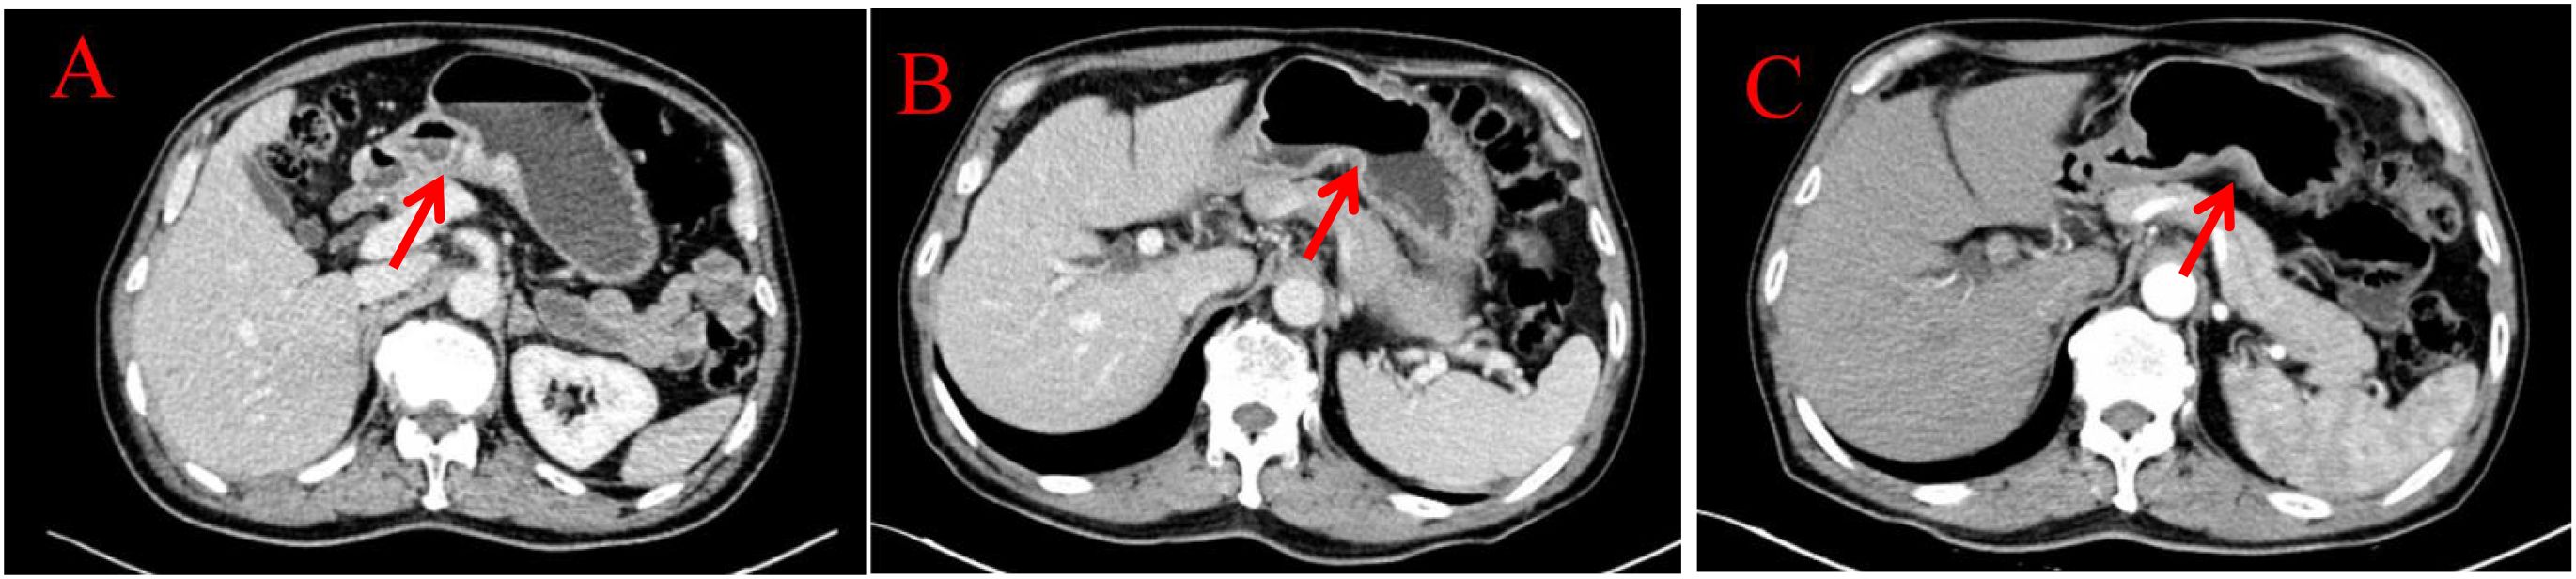

Endoscopic Examination is shown in Figure 2. Pathological Examination is shown in Figure 1. Imaging examinations of the changes in lung, gastric, intestinal and bone lesions are shown in Figures 3–5. The timeline of the diagnosis and treatment process is shown in Figure 6.

Figure 4. Imaging examinations of the changes in gastric lesions: (A) (2024.4.18) The gastric cavity is poorly filled, and there is a suspected slight thickening of the gastric wall locally. (B) (2024.12.10) The gastric cavity is poorly filled, and the gastric wall is thickened, similar to before. (C) (2025.3.26) The gastric cavity is poorly filled, and the gastric wall at the lesser curvature of the stomach is slightly thickened, similar to before.